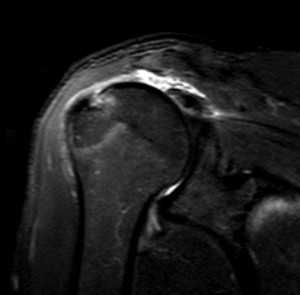

Разрыв вращательной манжеты – также характерное повреждение области плеча – может быть связан как с травмой, так и дегенеративными процессами. Разрывы вращательной манжеты бывают полные и неполные. Кроме того, по МРТ плечевого сустава выделяют 3 градации, в основе которых лежит не только изменение сигнала на Т2-зависимых томограммах, но и морфологические изменения сухожилия.

МРТ. Корональная Т2-зависимая томограмма с подавлением сигнала от жира. Полный разрыв сухожилия надостной мышцы.

При МРТ плечевого сустава косвенным признаком разрыва вращательной манжеты служит высокий сигнал на Т2-взвешенных от поверхности сустава до субакромиальной (субдельтовидной) сумки. Частичные разрывы чаще всего по передней поверхности сухожилия м.supraspinatus, реже примыкая к большой бугристости или сухожилия м. infraspinatus.

МРТ плечевого сустава. Т2-взвешенная корональная МРТ. Субакромиальное скопление жидкости – косвенный признак разрыва вращательной манжеты.